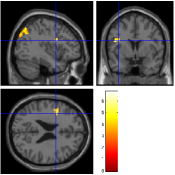

Concerning the Lc-Rc contrast on the data acquired with , Fig. 7 [top] shows that all reconstruction methods enable to retrieve the expected activation in the right precentral gyrus. However, when looking more carefully at the statistical results (see Tab. 2), our pipeline and especially the 4D-UWR-SENSE algorithm retrieves an additional cluster in the right middle frontal gyrus. On data acquired with , the same Lc-Rc contrast elicits similar activations, i.e. in the same region. As demonstrated in Fig. 7 [bottom], this activity is enhanced when pMRI reconstruction is performed with our pipeline. Quantitative results in Tab. 2 confirm numerically what can be observed in Fig. 7: larger clusters with higher local -scores are detected using the 4D-UWR-SENSE algorithm, both for and . Also, a larger number of clusters is retrieved for using wavelet-based regularization.

In order to investigate the smoothing effect introduced by our algorithm, spatial smoothing in the pre-processing pipeline has been turned off and statistical results are illustrated in Fig. 7 [right] and Tab. 2 (Unsmoothed 4D-UWR-SENSE). As expected, qualitative and quantitative results show that deactivating the spatial smoothing gives slightly higher -score values for activation maxima. However, smaller activated clusters are detected compared to results obtained based on smoothed data. As regards the temporal regularization effect, statistical results (not shown here) obtained with 3D-UWR-SENSE reconstructed images show intermediate performance which lies between those of the 2D (UWR-SENSE) and 4D (4D-UWR-SENSE) versions. Indeed, such a regularization helps improving the BOLD signal contrast which allows us to retrieve higher activation peaks.

| mSENSE | UWR-SENSE | 4D-UWR-SENSE | Unsmoothed 4D-UWR-SENSE | |

|---|---|---|---|---|

|

|

|

|

|

|

|

|

|

| cluster-level | voxel-level | |||||

| p-value | Size | p-value | T-score | Position | ||

| mSENSE | 79 | 6.49 | 38 -26 66 | |||

| UWR-SENSE | 144 | 0.004 | 5.82 | 40 -22 63 | ||

| 21 | 0.064 | 4.19 | 24 -8 63 | |||

| 4D-UWR-SENSE | 189 | 0.001 | 7.03 | 34 -24 69 | ||

| 53 | 0.001 | 4.98 | 50 -18 42 | |||

| 47 | 0.001 | 5.14 | 32 -6 66 | |||

| Unsmoothed 4D-UWR-SENSE | 112 | 0.001 | 7.26 | 34 -24 69 | ||

| 21 | 0.001 | 4.77 | 32 -6 66 | |||

| 19 | 0.001 | 4.98 | 50 -18 42 | |||

| mSENSE | 0.006 | 21 | 0.295 | 4.82 | 34 -28 63 | |

| UWR-SENSE | 33 | 0.120 | 5.06 | 40 -24 66 | ||

| 4D-UWR-SENSE | 51 | 0.006 | 5.57 | 40 -24 66 | ||

| Unsmoothed 4D-UWR-SENSE | 25 | 0.001 | 5.7 | 40 -24 66 | ||

Fig. 8 reports on the robustness of the proposed pMRI pipeline to the between-subject variability for this motor contrast. Since sensory functions are expected to generate larger BOLD effects (higher SNR) and appear more stable, our comparison takes place at . Two subject-level Student’s -maps reconstructed using the different pMRI algorithms are compared in Fig. 8. For the second subject, one can observe that the mSENSE algorithm fails to detect any activation cluster in the right motor cortex. By contrast, our 4D-UWR-SENSE method retrieves more coherent activity for this second subject in the expected region.